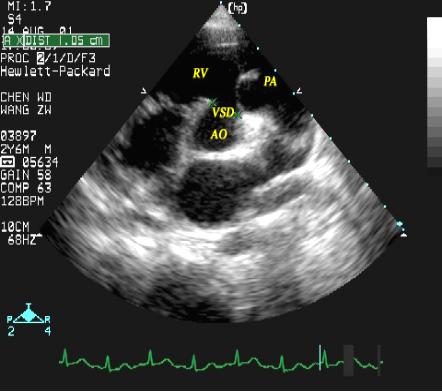

室间隔缺损:超声心动图表现

室间隔缺损(流出道部)